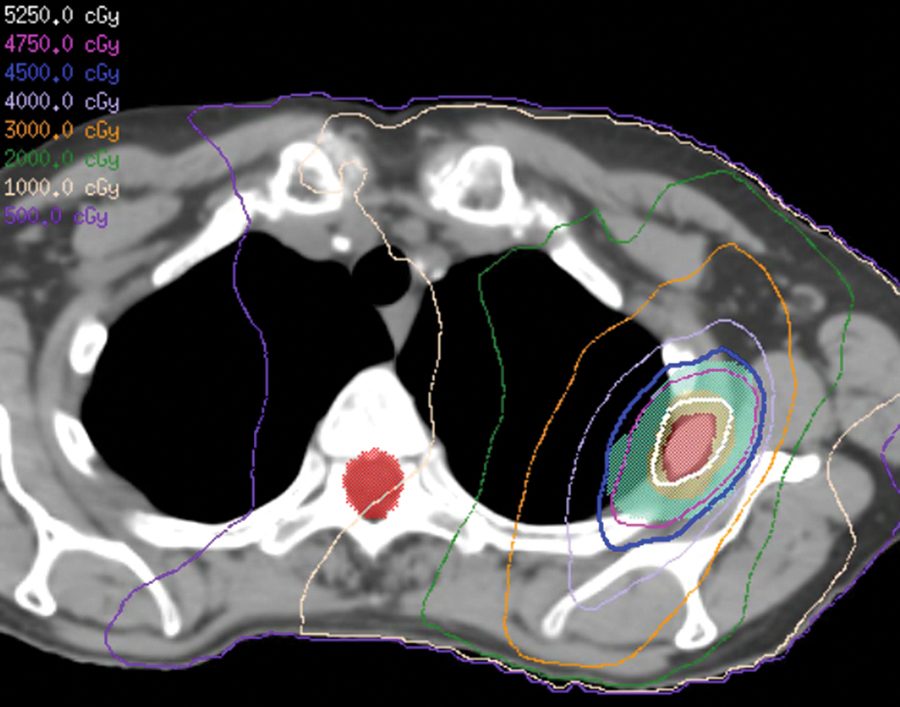

La terapia de protones para el cáncer de mama puede evitar daño en el corazón

El ensayo compara la cardiotoxicidad de la administración de radioterapia basada en protones y en fotones a la mama/la pared torácica y los ganglios linfáticos